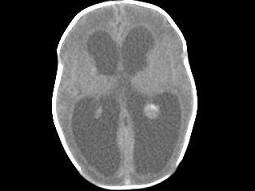

问题 1岁,女,头颅呈球状,颅骨透光试验阳性,请结合CT图片,选择最可能的诊断 ( )

选项 A、先天性脑积水 B、重度脑积水 C、慢性双侧性巨大硬膜下血肿 D、水瘤 E、脑严重缺血

答案 A